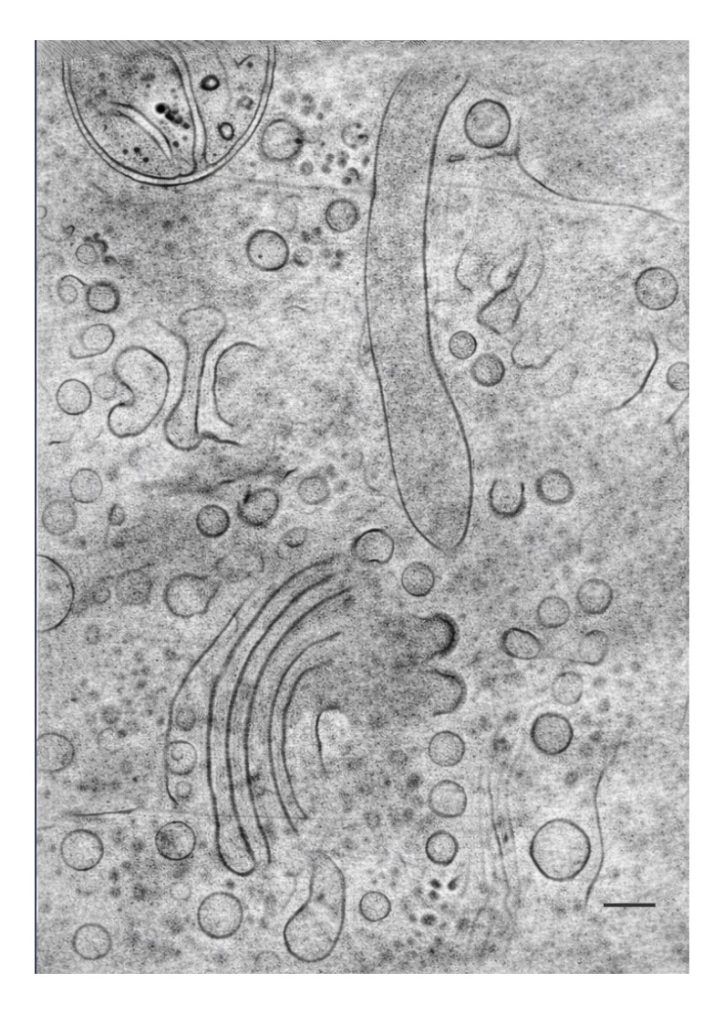

According to Prof. Segal-Peretz, “Using the new instrumentation, Technion researchers will be able to observe a wide range of phenomena at molecular resolution while preserving the natural environment of the molecules by rapidly freezing them to temperatures of minus 170°C. This will make it possible, for example, to see how a drug binds to its target protein to perform its therapeutic function, or how a human cell transports molecules through the nuclear envelope to initiate the expression of specific genes. Another example is deciphering the mechanism by which polymers self-organize to impart desired properties for various engineering applications.”

Photo credit: Rami Shlush